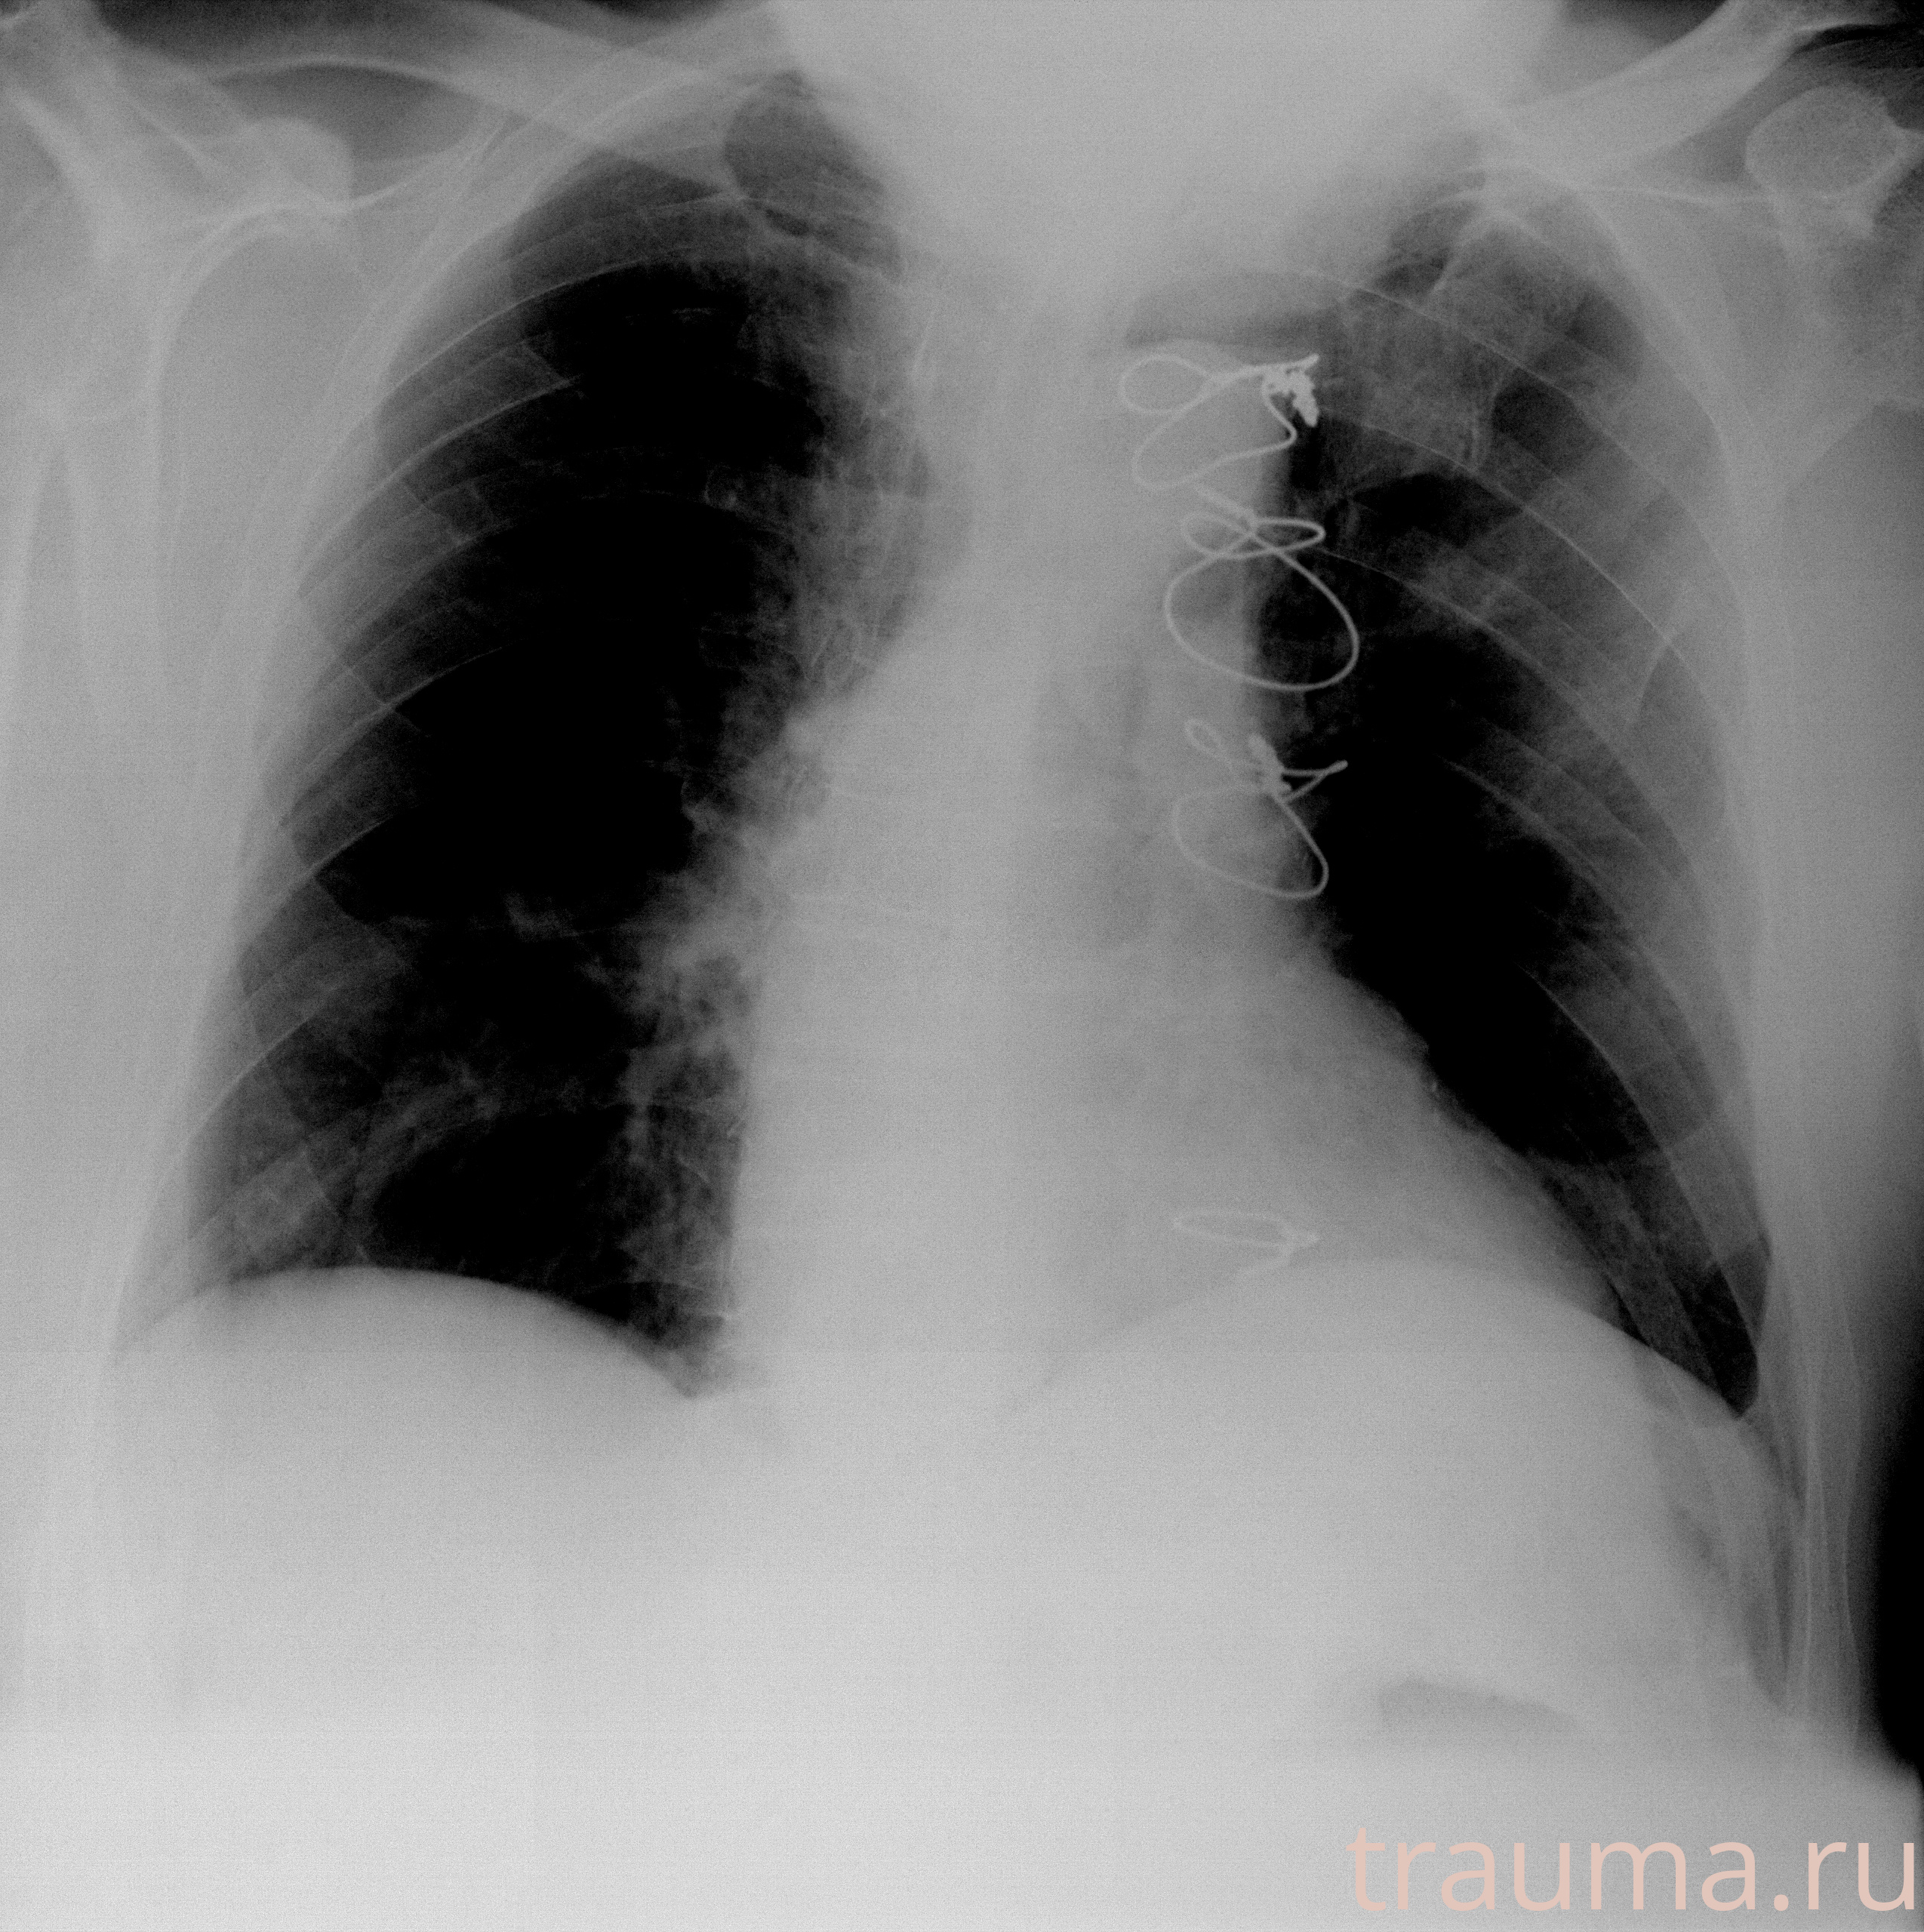

Рентгенограммы

Рентген на дому: по вашему адресу приезжает врач-рентгенолог, травматолог-ортопед с мобильным рентгеновским аппаратом, проводит диагностику травмы или заболевания, делает необходимые рентгенограммы, дает рекомендации по дальнейшему лечению. Получить качественные снимки в домашних условиях возможно благодаря уникальной методике, разработанной МосРентген Центром для института  Склифосовского

Яркость: 1   Контраст: 1   Инвертировать: 0 Увеличение: 1

Перетаскивайте мышь вверх/вниз для контраста, влево/право для яркости. Прокрутка колесом изменяет масштаб. Нажмите Сбросить для возврата к исходному изображению. При увеличении держите мышь в той области, которую хотите рассмотреть.